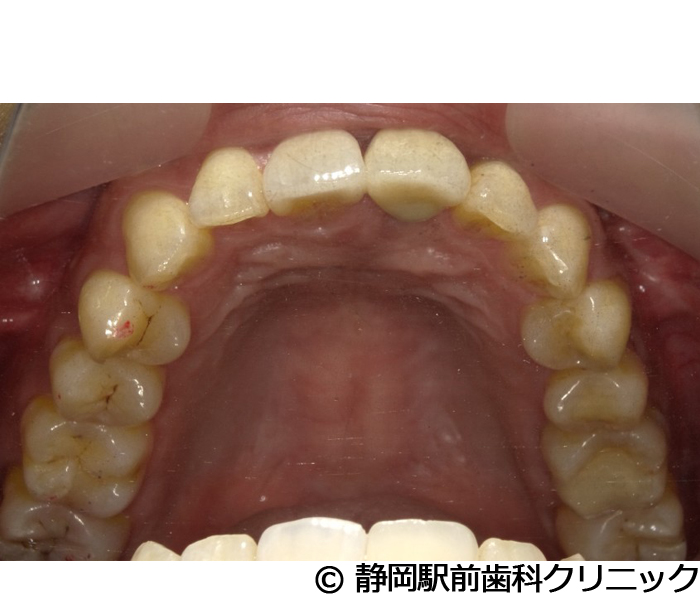

【症例4】全顎的インプラントとセラミックによる審美補綴

- 治療前

- 治療後

- 治療名

- 全顎的インプラントとセラミックによる審美補綴

- 費用

- 1,200,000円(税込)

- 期間

- 1年3ヵ月

治療内容

-

患者様の症状

左上ブリッジが歯根破折してしまい、他院で入れ歯を作ったが使い心地がよくないため、インプラント治療希望。

治療方法

抜歯後、骨治癒後にCTを撮影して、綿密に治療計画を立てた。上顎洞の距離やインプラント同士のバランスを熟慮し、インプラントを埋入した。全体的な噛み合わせの調整を重ねた後、人工歯を被せて咬合と見た目の回復を行った。

治療結果

入れ歯のような違和感が全くなく、力を入れてしっかり噛むことができるので、食事することが楽しくなったとご満足いただけました。見た目もセラミックの歯が入ったので、自分の歯が戻ったようだと喜んでいただきました。

※治療結果は個人差があります。

治療を行う上での注意点(リスク・副作用)

術後は、出血、腫れ、痛みなどが出る可能性があります。